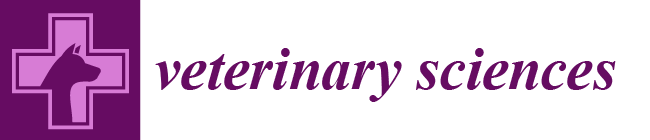

3.1. Characteristics of Dogs

3.4. Expression Profile of the Studied Cfa-Mirnas in the Investigated Groups Compared to the Control Group